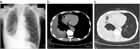

1. 無気肺とは肺組織が虚脱し、肺の含気が低下した状態である。

1. 閉塞性無気肺(腫瘍、粘液栓、異物、気管支結核など)と非閉塞性無気肺(炎症などによる肺実質の虚脱、受動性無気肺、円形無気肺など)に大別される。

1. 胸部X線撮影で無気肺が疑われたら、まずは胸部造影CTで鑑別をすすめ、必要に応じ喀痰培養、喀痰細胞診、気管支鏡などを行う。